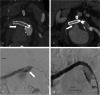

Objective: To present a case series of spontaneous structural failure of bridging stentgrafts (BSGs) after branched endovascular aortic repair (bEVAR), as well as their failure types and their detection. While bEVAR is a safe and effective procedure, one main limitation is the reintervention rate associated with the BSGs. Structural failure of BSGs, defined as fabric disruption, stent fracture with leak or complete separation is a major cause for reinterventions and difficult to detect in computed tomography angiography (CTA).

Results: Twenty-three BSG failures were detected in 12 patients with only 43% directly identified in CTA, after a mean of 21.4 months after implantation. The BSGs were Advanta (n = 4), E-Ventus (n = 16) and BeGraft (n = 3) in 10 renal, 9 superior mesenteric, and 4 celiac branches. Religning with another BSG was successful in 20/22 cases, one BSG failure necessitated renal branch embolization (organ loss), and one mesenteric bypass surgery. Two reintervention-related mortalities occurred.

Conclusion: Structural failure of BSGs is a serious limitation for bEVAR, which can result in high reintervention rates and serious complications. BSG failure typically occurs in single-layer types and events are clustered in patients. The necessary reinterventions carry serious morbidity and mortality. Since the use as BSG in bEVAR is off-label with all current BSG manufacturers, caution is advised regarding patient-informed consent.